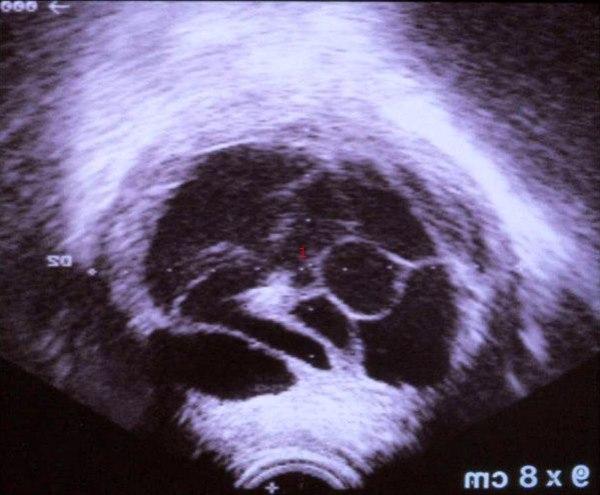

Degenerativt myom

1. Myom med dannelse av cyster